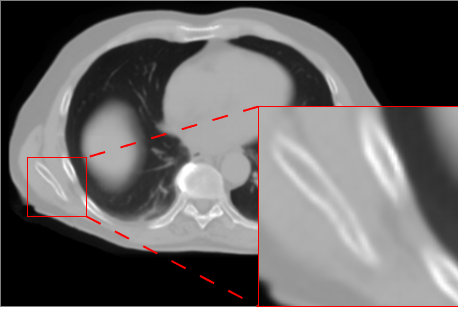

6.2 CBCT to CT translation (Task 2)

Figure 3 presents qualitative results for the CBCT-to-CT translation task on the HN dataset. The displayed axial slices include a lesion visible inside the brain, allowing a focused assessment of reconstruction quality. Visual inspection shows that AFP-based models generally produce slightly sharper and more accurate reconstructions than L1-only models, with nnResU-Net providing the most precise delineation. In particular, the combination of AFP with nnResU-Net better reconstructs the lesion compared to other configurations.

![]() |

| Input CBCT | nnU-Net L1 | nnU-Net L1 + AFP |

| Real CT | nnResU-Net L1 | nnResU-Net L1 + AFP |

Quantitative results in Table 5 and Table 6 are computed on the fused HN, AB, and TH datasets. As observed for Task 1, intensity-based metrics are best for nnResU-Net with L1 loss, reflecting the direct optimization of pixel-wise MAE, PSNR, and MS-SSIM. Conversely, segmentation-based metrics show a clear advantage for AFP, with nnResU-Net + AFP achieving the highest DICE and lowest HD95, in line with visual observations of more accurate anatomical boundaries and lesion reconstruction. Overall, the trends across models and losses are consistent with Task 1, confirming the benefits of AFP for improving structure-level fidelity without necessarily maximizing intensity-based metrics.